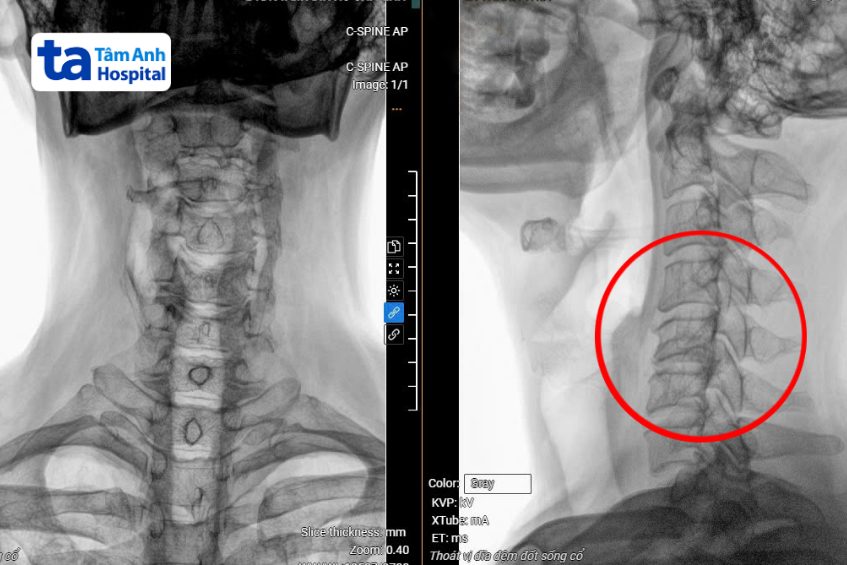

Kết quả chụp MRI 3 Tesla tại Bệnh viện Đa khoa Tâm Anh TP HCM cho thấy anh An bị thoát vị đĩa đệm cột sống cổ nặng từ C3 đến C7, gù cột sống cổ, chèn ép làm tổn thương tủy C5, C6 (vị trí đốt sống cổ thứ 5 và thứ 6).

Ngoài ra, cột sống thắt lưng của anh cũng bị thoát vị và chèn ép thần kinh khá nặng ở tầng L4, L5 (vị trí đốt sống lưng thứ 4 và thứ 5). Hiện anh bị yếu tay chân phải, đau nhiều ở cổ vai gáy và lưng, khó thực hiện các hoạt động khiêng vác nặng hoặc cần sự tỉ mỉ như cài nút áo, cầm đũa.